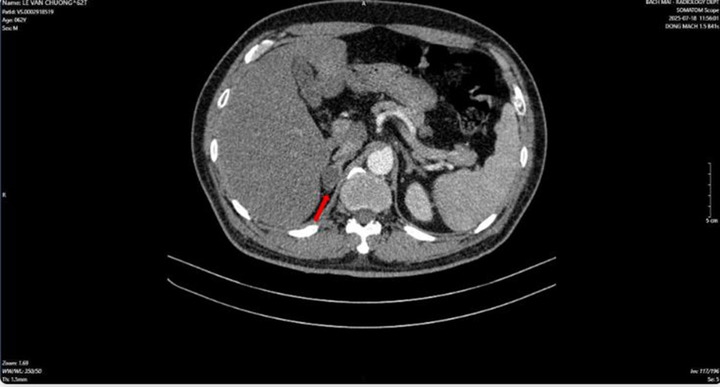

Thông tin từ Bệnh viện Bạch Mai, nam bệnh nhân nhập viện trong tình trạng tiểu khó kéo dài. Qua thăm khám và thực hiện các kỹ thuật cận lâm sàng như chụp cắt lớp vi tính, cộng hưởng từ, xạ hình xương và đặc biệt là PET/CT, các bác sĩ phát hiện tổn thương tại tuyến tiền liệt cùng nhiều khối u ở phổi, tuyến thượng thận và xương.

Kết quả sinh thiết và phân tích mô bệnh học kết hợp hóa mô miễn dịch giúp làm rõ: khối u phổi là ung thư biểu mô tuyến của phổi, trong khi khối u tuyến tiền liệt là ung thư biểu mô tuyến với điểm Gleason 9 - thuộc nhóm nguy cơ cao. Hai loại ung thư này có nguồn gốc hoàn toàn khác nhau, không phải di căn chéo.

Sau khi hội chẩn chuyên môn, các bác sĩ xây dựng phác đồ điều trị phù hợp, ưu tiên kiểm soát bệnh toàn thân. Cụ thể, bệnh nhân được chỉ định hóa trị ung thư phổi bằng phác đồ Pemetrexed kết hợp Carboplatin, đồng thời điều trị nội tiết cho ung thư tuyến tiền liệt bằng Degarelix.